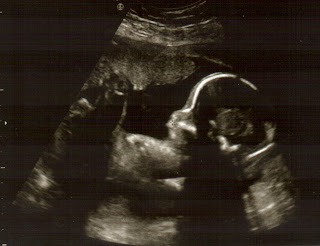

A Rafaela está a crescer no percentil 50, está com 1,800kg, o dr diz que está rechonchuda(não é só a mãe que come) mostrou-nos a carinha dela, abria e fexava a boca e os olhos. Abriu e fexou as mãos como se nos estivesse a "dizer adeus". Em cada ecografia é uma emoção :D

Como disse o medico está quase, mandou-me marcar mais uma consulta, dia 12 de fevereiro e nessa ainda vou fazer ecografia :D